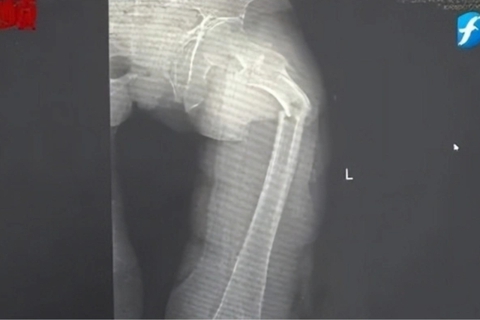

Xương đùi của người đàn ông 35 tuổi gãy làm đôi sau một cơn ho (Ảnh BV cung cấp)

Đến nửa đêm, anh Cung bị giật mình tỉnh giấc vì cơn đau ở đùi. Anh phát hiện ra mình không thể đi lại được nhưng cố chờ đến trời sáng hẳn rồi nhờ người nhà đưa đi bệnh viện. Kết quả chụp X-quang tại Bệnh viện Nhân dân số 2 Phúc Kiến (Trung Quốc) khiến anh Cung sốc nặng: xương đùi trái của anh bị gãy làm hai mảnh chỉ vì một cái ho.

Bác sĩ Đông Trung, Trưởng khoa Chấn thương và Chỉnh hình của bệnh viện cho biết anh Cung bị gãy xương bệnh lý, xảy ra do loãng xương sớm rất nghiêm trọng. Dù mới 35 tuổi nhưng xương của anh Cung được bác sĩ nói vui là “xốp như tổ ong”, khối lượng xương tương đương với một cụ già 80 tuổi.